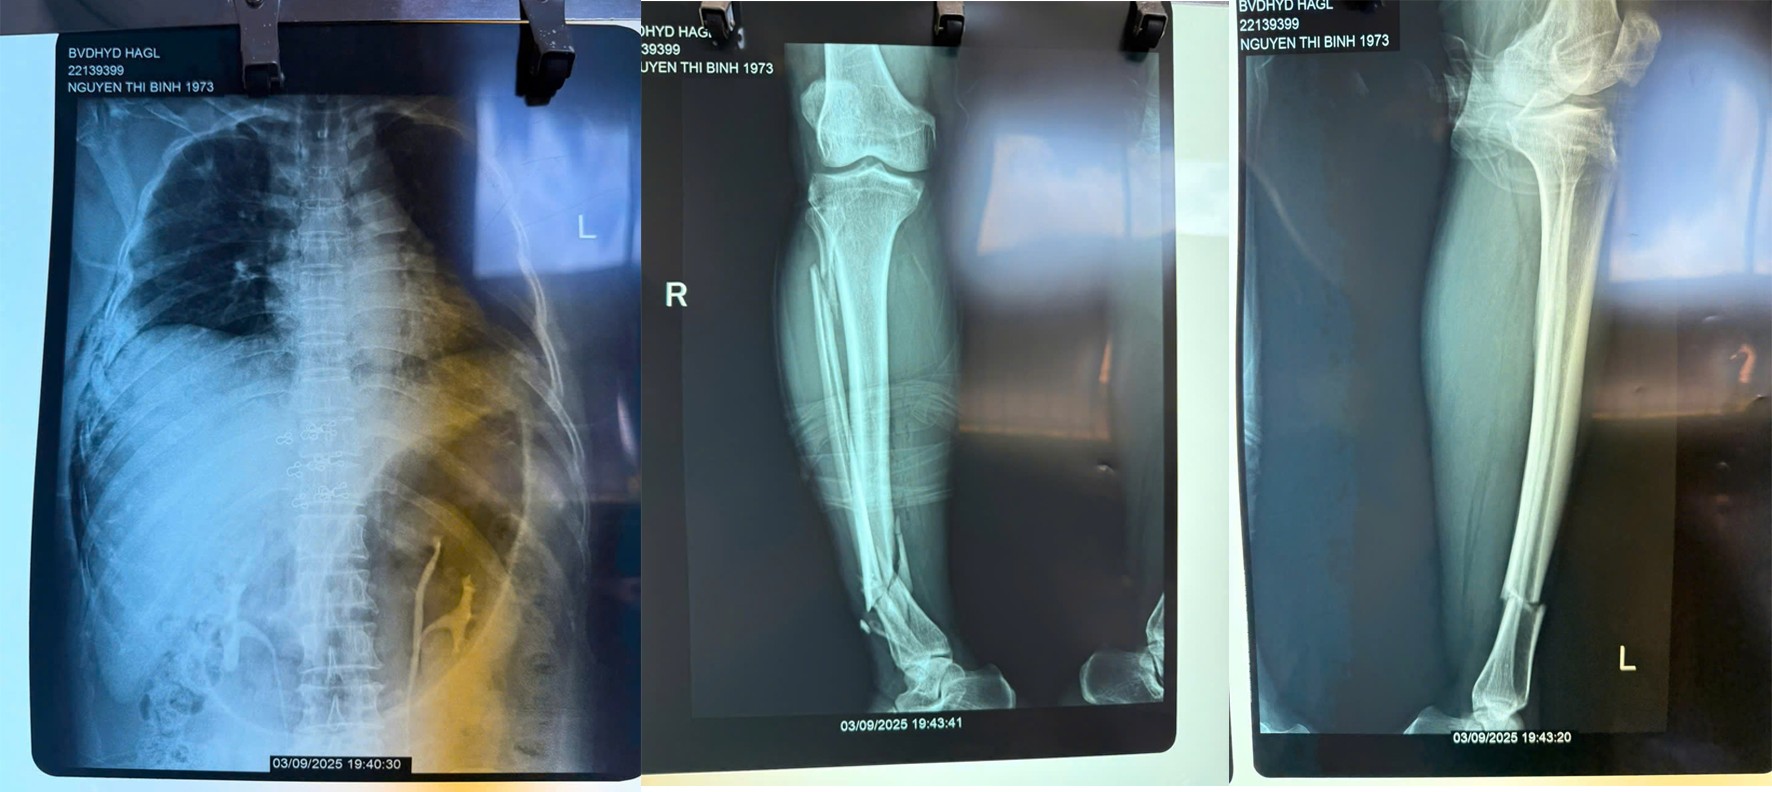

Khi tiếp nhận tại khoa Cấp cứu, chị B. đang trong tình trạng sốc chấn thương, mạch nhanh, huyết áp tụt. Ngay lập tức, đội ngũ y bác sĩ đã tiến hành hồi sức, giảm đau, xét nghiệm và chẩn đoán hình ảnh. Kết quả cho thấy bệnh nhân bị đa chấn thương nghiêm trọng: gãy nhiều xương sườn hai bên, tràn dịch, tràn khí màng phổi phải, gãy mỏm ngang cột sống D12 – L1, gãy phức tạp đầu trên xương đùi trái và gãy đầu dưới xương cẳng chân hai bên.

| Hình ảnh X-Quang xương sườn, chân phải, chân trái |